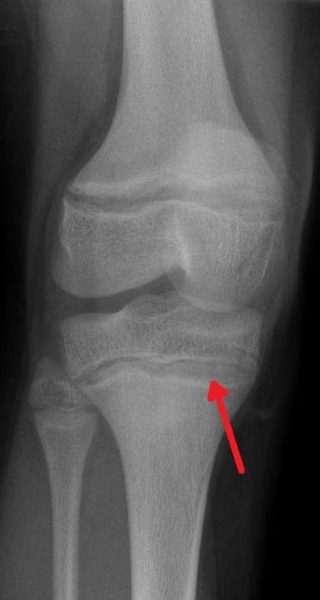

fot.Dr Abhijit Datir / CC BY-SA 3.0

Zagęszczone (sklerotyczne) linie przynasadowe spowodowane zatruciem ołowiem